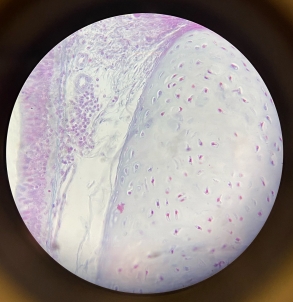

Dense Regular Collagenous Connective Tissue (Fibrous Tissue)

Dense Regular Elastic Connective Tissue (Elastic Tissue)

Hyaline Cartilage

Elastic Cartilage

Hyaline Cartilage

Fibrocartilage

Bone

Bone

Bone

Bone

Bone